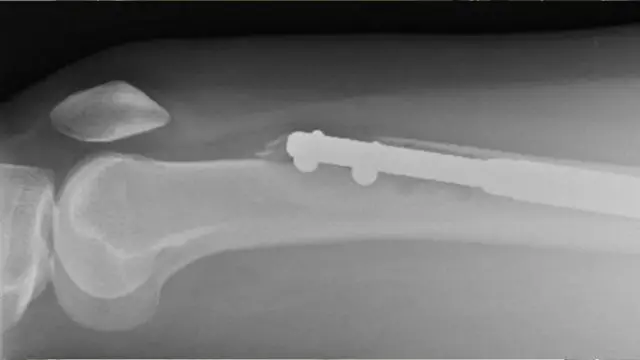

اس طرح کی سرجری میں تھوڑا درد ہوتا ہے کیونکہ ٹانگ کی ہڈی کو دو حصوں میں توڑ دیا جاتا ہے اور ان کے درمیان دھات کا ایک راڈ ڈال دیا جاتا ہے۔

اس دھات کے راڈ کو آہستہ آہستہ ٹوٹی ہڈی کے دو حصوں کے درمیان طے شدہ لمبائی تک بڑھایا جاتا ہے تاکہ مریض کا قد بڑھ جائے۔

اگلے دن ایلین کا سکین کیا گیا اور انھیں جو خدشہ تھا وہ درست ثابت ہوا۔ ان کے بائیں پاؤں میں ڈالی گئی کیل فیمر یعنی جسم کی سب سے مضبوط ہڈی کو چھید کر باہر نکل آئی تھی۔

چھ ہفتے بعد ایک سکین سے پتہ چلا کہ ان کی دائیں ٹانگ کی ہڈیوں نے بڑھ کر جڑنا بند کر دیا تھا۔ ان کی ٹانگ میں فیمر کیح ہڈی کے دو حصے دھات کے راڈ سے جڑے ہوئے تھے۔

جب ایلین ڈاکٹر سے ملیں تو انھوں نے میلان کے ایک کلینک میں ایک اور آپریشن کرنے کا فیصلہ کیا۔ وہ میلان کے اس کلینک میں بھی پریکٹس کر رہے تھے۔ اپریل 2017 میں ڈاکٹر نے ایلین کی بائیں ٹانگ کو بڑا کرنے کے لیے سرجری کی۔ اس دوران ہڈیوں کی نشوونما کو تیز کرنے کے لیے دائیں ٹانگ میں بون میرو کا انجکشن لگایا گیا۔

وہ کہتی ہیں کہ ’ڈاکٹر گیوشے نے مجھے بتایا کہ جب وہ کیل نکال رہے تھے تو وہ ٹوٹ گئی۔ اُن کے پاس ایک دوسرے مریض کا کیل تھا جسے انھوں نے میرے پاؤں میں ڈال دیا۔‘ اس کے ساتھ انھوں نے بتایا کہ اس پر مزید خرچ آئے گا۔